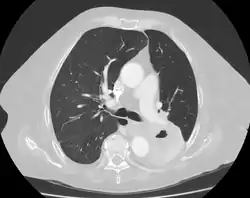

Diagnosis of a lung cavity is made with a chest X-ray or CT scan of the chest,[2] which helps to exclude mimics like lung cysts, emphysema, bullae, and cystic bronchiectasis.[5] Once an imaging diagnosis has been made, a person’s symptoms can be used to further narrow the differential diagnosis. For example, recent onset of fever and productive cough suggest an infection, while a chronic cough, fatigue, and unintentional weight loss suggest cancer or tuberculosis.[2] Symptoms of a lung cavity due to infection can include fever, chills, and cough.[5] Knowing how long someone has had symptoms for or how long a cavity has been present on imaging can also help to narrow down the diagnosis. If symptoms or imaging findings have been present for less than three months, the cause is most likely an acute infection; if they have been present for more than three months, the cause is most likely a chronic infection, cancer, or an autoimmune disease.[5]

Cavitation of a lung squamous carcinoma, infrahilar, affecting the left lower lobe. 72-year-old woman.

The most common cause of a single lung cavity is lung cancer.[4] Usually, the cavity forms because the cancer grows more rapidly than its blood supply, resulting in necrosis (cell death) in the central part of the cancer. 81% of lung cancers that develop cavities over-express epidermal growth factor receptor (EGFR), which could be related to rapid growth, central necrosis, and cavity formation.[11] 11% of primary lung cancers (cancers that start in the lung) have cavities that can be seen on chest X-ray; 22% of primary lung cancers will have cavities on CT, which is more sensitive.[2] Squamous-cell carcinoma of the lung is more likely to develop cavitations than lung adenocarcinoma or large-cell lung carcinoma.[2] Other primary cancers of the lung, such as lymphoma and Kaposi’s sarcoma, can also cavitate, especially in people with AIDS.[7] Lung cancers that develop cavities are associated with a poor prognosis (worse outcomes). Cancers that metastasize (spread) to the lung can also develop cavitations, but this is only seen about 4% of the time on X-ray. Metastatic cancers of squamous cell origin are also more likely to cavitate than cancers of other origins.[7] Both chemotherapy (drugs to treat cancer) and radiofrequency ablation (destroying cancer with radio waves) can cause lung cancers to develop cavities, which is a sign of a good response to treatment.[2] It is possible to have both an infection and lung cancer in the same cavity; the most common combination is primary lung cancer and tuberculosis.[7]